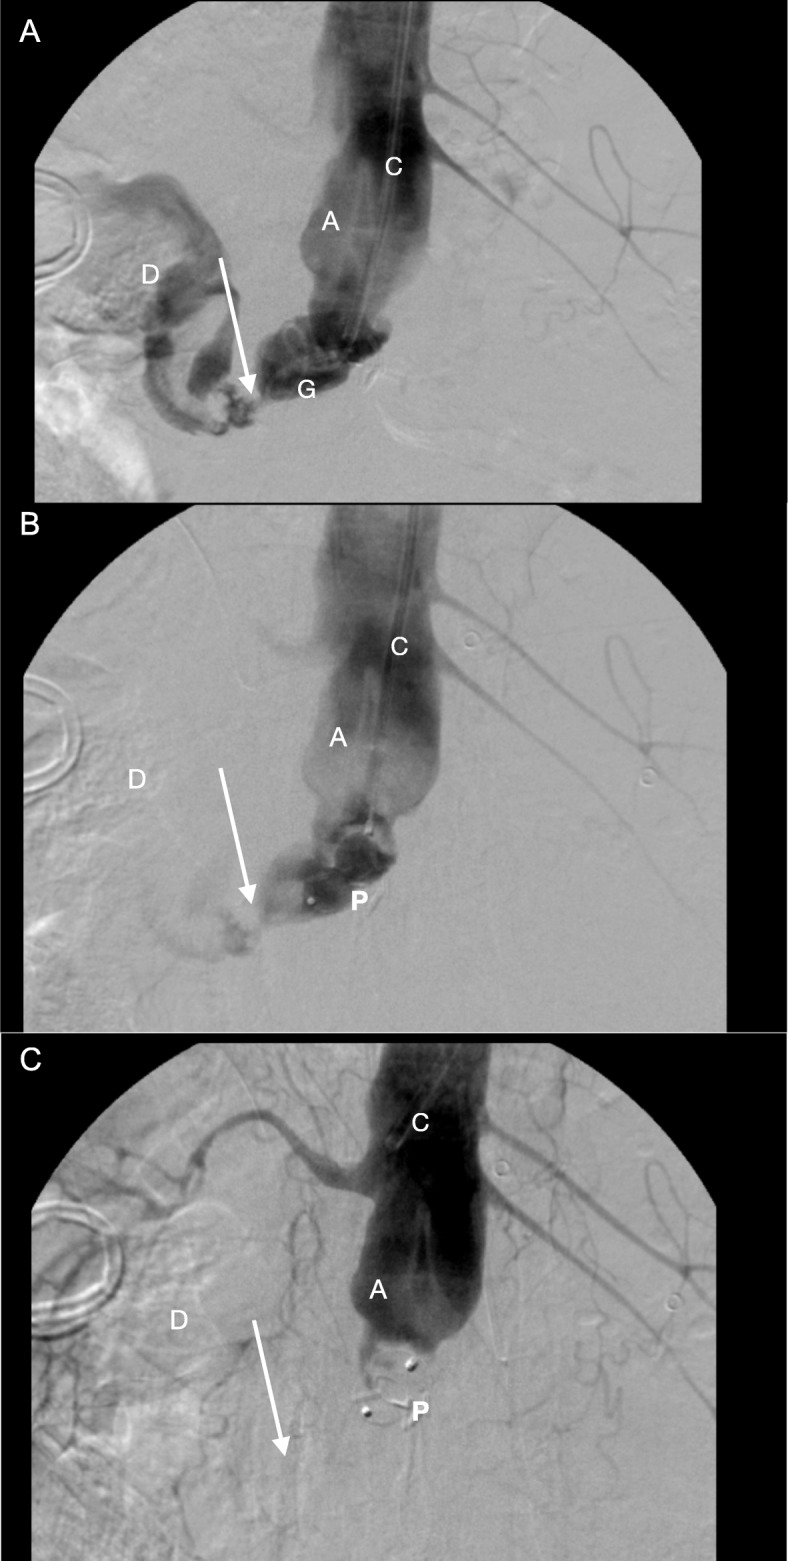

Fig. 2.

Angiography and the placement of the Amplatzer® Vascular Plug in the aortic stump. Angiography via the axillo-bi-femoral bypass demonstrating the infrarenal aortic stump (a), the duodenum (d) and the ADF marked with the arrow (↓). The angiographic catheter is marked with C and the guide wire with G. The upper graph (a) demonstrates contrast passage from the aorta through the ADF towards the duodenum. The middle graph (b) was taken 5 min following release of a 16-mm Amplatzer® Vascular Plug (P) within the aortic stump, and demonstrates minor contrast passage from the aortic stump towards the duodenal loop. The lower graph (c), 23 min later, demonstrates successful closure of the aortic stump with no further contrast leakage through the ADF